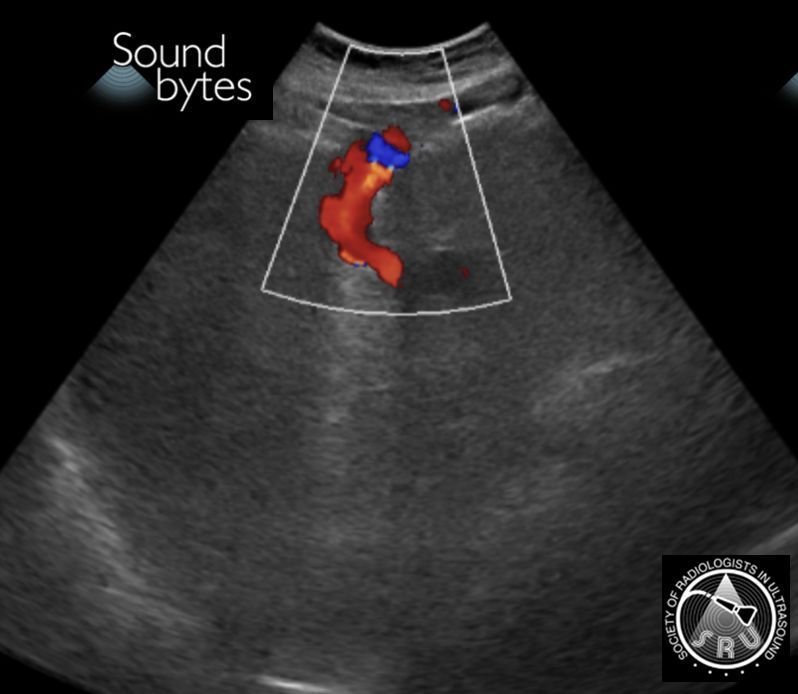

Dx: (Fat containing) *Indirect* Inguinal Hernia

Findings: Herniation of intraabdominal fat between the inferior epigastric and the external iliac vessels.

Case courtesy of Dr. Neel Patel, OHSU